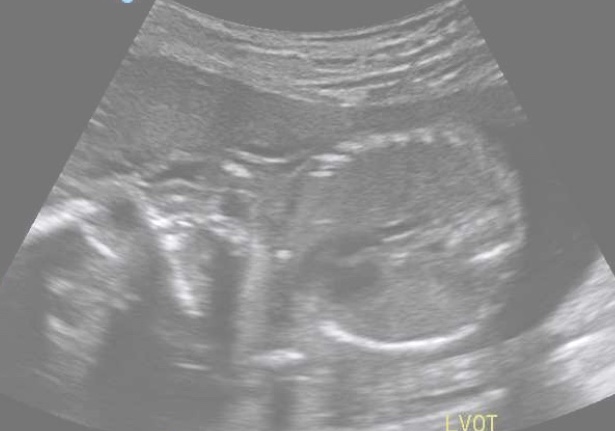

A big long cord connected them together.

It sent yummy food from Pops to Nick, so they could grow and play.